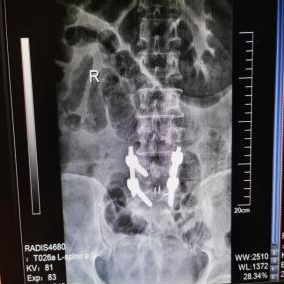

4月23日,贵州航天医院第58次晨读会由我院骨科副主任医师张艳金作学术交流,他以“加速康复指导下的快速手术”为题,详细讲解了老年股骨粗隆间骨折与儿童四肢骨折的临床诊疗难点,结合加速康复外科(ERAS)核心理念,重点阐述了ERAS理念在两大人群中的创新实践,实现患者入院后6至24小时内即可接受手术治疗。针对老年髋部骨折患者,提出通过多学科协作(MDT)与微创手术优化围术期管理,在确保安全前提下缩短术前等待时间,实施精准化麻醉及术后康复方案,可有效降低并发症发生率、改善患者生活质量和预后效果。在儿童骨折领域,强调微创术式与心理干预并行的双轨策略,既减少手术创伤对骨骼发育的影响,同时关注患儿心理疏导,实现生理功能与心理健康同步康复。并通过典型案例的影像学资料与随访数据,直观展示了ERAS理念指导下骨科治疗模式的创新成果。 贵州航天医院骨科 专家简介 赵学平 中共党员,骨科党支部书记、主任,主任医师 临床擅长:从事骨科临床工作30余年,对骨科常见疾病的诊治具有丰富的临床经验。 世界中医药联合会脊柱康复专业委员会常务理事,中华中医药学会整脊分会常务委员,中国中西医结合学会骨伤科分会肢体矫形功能重建与康复专家委员会常务委员,中国研究性医院学会骨科创新与转换专业委员会关节外科学组保髋工作委员会常委,中国康复技术转化及发展促进会骨外科与康复技术转化专业委员会常务委员,泛珠三角区域运动医学联盟(PPRD-SMA)理事会常务理事,中国研究型医院学会运动医学专业委员会委员,贵州省中医药学会整脊分会副主任委员,贵州省中西医结合学会银质针专业委员会副主任委员,贵州省康复医学会骨与关节专业委员会常务委员,贵州省人民医院骨科专科联盟常务理事,贵州省康复医学会骨内科专业委员会常务委员,中华医学会贵州省骨科学会委员,贵州省康复医学会脊柱脊髓专业委员会常务委员,贵州省运动医学分会委员,贵州省康复医学会骨与软组织肿瘤专业委员会委员,遵义市医学会创伤分会副主任委员,贵州省康复医学会骨内科专业委员会遵义地区分会常务委员,遵义市医疗事故鉴定、伤残鉴定、工伤鉴定、司法鉴定专家。 长期从事骨科临床研究及教学工作,在国家级、省部级杂志发表论文20余篇,SCI论文2篇,参与主编骨科专著2部,主持省部级科研项目2项,参与指导省部级、市级科研项目6项。 陈明勇 骨科副主任,副主任医师 临床擅长:从事创伤骨科工作约20年,对骨缺损、骨不连、骨肿瘤、肢体畸形等的肢体矫形重建及功能重建,慢性化脓性骨髓炎的根治治疗、糖尿病足的保肢治疗、快速康复理念(ERAS)下的老年骨折的诊治,四肢复杂骨折的诊治,四肢骨折等微创手术治疗具有丰富的临床经验。 2004年毕业于遵义医学院临床专业,曾在中国人民解放军总医院、广西医科大学第一附属医院、上海第六人民医院骨科进修。中国中西医结合学会骨伤科专业委员会横向骨搬移治疗糖尿病足及微血管网再生学组首届委员,遵义市医学会创伤分会常务委员。 瞿 辉 中共党员,骨科副主任医师 临床擅长:对骨科的常见病、关节外科、脊柱外科及运动医学疾病的诊治具有丰富的临床经验,熟练掌握骨科手术操作技术。 毕业于遵义医学院临床医学系,2005年前往广州中山大学第一附院骨显微医学部进修学习,2011年前往成都华西医院进修学习,并多次在省内外学习骨科相关知识,是中华医学会骨科分会会员。 赵兴东 骨科主任医师 临床擅长:擅长骨科的常见病及各种创伤、四肢骨折创伤修复、骨感染、手足疾病的诊治和手足体表畸形的矫形整复,熟练掌握骨科四肢骨病及创伤的手术操作技术,尤其在四肢关节复杂性损伤、手足外伤、组织缺损创面、难治创面的皮瓣修复方面及平足、高弓足矫形方面及四肢慢性疼痛诊治、康复方面具有丰富的临床经验。 硕士研究生,毕业于遵义医学院临床外科系,2015年前往山东省立医院手足外科进修学习;遵义市医学分会创伤分会第一、二届委员,遵义市手外科医学会第二委届员会常务委员;在省级及省级以上期刊发表文章9篇,参编著作2部,参与主持并完成市级课题1项,参与市级课题2项、省级课题1项。 张艳金 中共党员,骨科副主任医师 临床擅长:从事骨外科工作16年,对复合伤、多发伤的救治、四肢骨干骨折、关节周围骨折、骨肿瘤、骨髓炎等诊治具有丰富的临床经验。 中共党员,硕士研究生,2006年本科毕业于山西医科大学第二临床医学院,2011年研究生毕业于北京军区总医院;在“老年COPD患者合并髋部骨折的诊治”国际合作课题组研究两年,在老年髋部骨折的诊治方面具有丰富的经验,并发表论文6篇;主持遵义市级课题1项,承担遵义医科大学的临床教学工作,获得遵义医科大学优秀带教老师荣誉。编撰有《骨科疾病诊疗精粹》一书,开展2项新技术,编撰地方规范《务川自治县创伤骨科常见疾病诊疗规范》一书。 张俊凯 骨科副主任医师 临床擅长:从事骨科临床工作28年,对创伤骨折、骨感染、骨缺损、骨不连等外科诊治,四肢骨折的微创手术治疗,四肢复杂骨折(如关节内粉碎性骨折、多发骨折等)的损伤控制及手术治疗等具有丰富的临床经验。 1995年毕业于遵义医学院临床专业,2009年前往复旦大学附属医院骨科进修1年。 卢懿明 中共党员,骨科副主任医师 临床擅长:从事骨科工作18年,对创伤骨折、四肢骨折的微创手术治疗、四肢复杂骨折(如关节内粉碎性骨折、多发骨折等)的损伤控制及手术治疗,尤其是髋部骨折的PFNA等微创技术,踝关节骨折、膝关节周围骨折的Mipo微创技术等具有丰富的临床经验,开展了4项新技术,发明6项新型专利技术。 2005年毕业于遵义医学院临床专业,2017年,前往南方医科大学第三附属医院骨科进修半年,回院后运用Mipo技术对骨干骨折及干骺端骨折的治疗技术,同时积极开展骨盆骨折、髋臼骨折腹直肌外侧切口的应用;发表了多篇专业论文,经常参与省内外学术交流会授课,获得医院荣誉称号多个。 邬夏荣 骨科副主任医师 临床擅长:从事骨科工作16年,对四肢复杂骨折、骨肿瘤的诊治,尤其是足踝创伤、慢性踝关节损伤、平足症等诊疗具有丰富的临床经验。 2006年毕业于遵义医科大学临床医学专业,曾在陆军军医大学西南医院进修学习,发表多篇骨科学术论文。 余德怀 中共党员,骨科副主任医师 临床擅长:从事骨科工作10余年,对运动医学、骨关节、脊柱外科常见病、多发病的诊治具有丰富的临床经验。 硕士研究生,2011年毕业于遵义医学院临床医学专业,曾前往遵义医科大学附属医院运动医学专业进修学习;是贵州省医学会运动医学分会青年委员,西部关节镜联盟委员;发表多篇骨科学术论文。 冯 乾 骨科副主任医师 临床擅长:从事骨科工作近20年,熟练掌握骨科多发病及常见病的诊治,尤其对脊柱退变性疾病的诊断及治疗具有丰富的临床经验,主要研究脊柱微创相关治疗方式,能熟练开展椎间孔镜及UBE。 曾前往北京大学第三医院进修学习疼痛及椎间孔镜、首都医科大学友谊医院专业进修脊柱内镜;是贵州省康复医学会第三届脊柱脊髓专业委员会委员;发明专利3项、发表脊柱外科专业论文多篇。 赵小锋 中共党员,骨科副主任医师 临床擅长:从事骨科临床工作11年,对骨科常见病、多发病诊疗有较为丰富的临床经验,擅长脊柱相关疾病诊断及治疗,尤其是颈、腰、腿疼痛疾病诊断及治疗,擅长胸腰椎骨折微创经皮穿刺内固定术、经皮穿刺椎体成形术、经皮穿刺脊柱内镜下腰椎间盘摘除术、单纯开创腰椎间盘摘除术、腰椎滑脱复位椎间植骨椎融合内固定术、腰椎管狭窄减压融合内固定术及人工髋、膝关节置换术等。 2012年毕业于遵义医学院外科学专业硕士研究生,2019年参加“遵义市115医学人才精英计划”于上海交通大学第一附属医院培训学习,2023年于北京大学第三人民医院脊柱外科进修学习,曾获得遵义市优秀医师荣誉称号。 遵义市手外科第一届委员,遵义市医学会创伤分会第一届委员,遵义市医学会创伤分会第二届委员,贵州省康复医学会第三届脊柱脊髓专业会委员,遵义市医学会烧伤与整形外科学分会委员,发表论文5篇,其中国家级核心期刊1篇,SCI论文1篇,主持市级课题1项并结题,参与市级课题2项。 贵州航天医院骨科 简介 基本情况 贵州航天医院骨科组建于20世纪60年代,前身是以创伤和断肢(断指)再植闻名于世的上海市第六人民医院骨科,中国断肢(断指)再植的奠基者、中科院院士陈仲伟等著名专家、学者多次莅临科室指导医疗、教学,是贵州省最早拥有专业骨科技术科室之一,在70年代开展了贵州省首例断肢(断指)再植手术。组建50余年来,诊治患者已逾百万,挽救了无数的伤病员,成为了保障遵义地区人民群众健康的重要支撑。 经过几代人的不懈努力,今天的骨科,已由创伤骨科发展至骨病、骨肿瘤、骨结核等领域,现有脊柱外科、关节外科、四肢创伤、手足外科四个亚专科,成为了集医疗、教学、科研于一体的综合学科,是贵州省临床重点专科、遵义市临床重点专科、遵义市骨科临床医学中心、遵义市基层骨科专科联盟理事长单位。 科室目前开放床位110张,共有医护人员50余人,副高级以上专家18人,硕士研究生15人。拥有一流骨科医疗设备多台,每年不定期选派优秀技术骨干到全国各大知名医学院校进修、学习、参观、交流,并邀请国内、国外知名专家教授来院进行交流、指导,通过不断引进国内外先进的诊疗技术,科室医疗技术水平稳步提升,为广大人民群众提供了优质的医疗服务。 专科特色 骨一科 (一)骨缺损、骨不连的肢体与功能重建 胫骨横向骨搬移技术治疗糖尿病足: (二)慢性骨髓炎的根治治疗 (三)肢体缺血性疾病如糖尿病足、脉管炎的保肢治疗 (四)皮瓣修复 (五)复杂创伤的治疗 (六)老年髋部骨折及小儿骨折快速手术 老年髋部骨折: 骨二科 (一)胸腰椎骨折微创经皮椎弓根螺钉固定术 (二)老年性骨质疏松性患者腰椎滑脱脊柱内固定术(骨水泥螺钉) (三)V形双通道脊柱内镜技术(VBE)腰椎融合术治疗腰椎退行性疾病 (四)老年性骨质疏松性骨折(PVP/PKP)术 (五)人工髋关节置换术 (六)双侧股骨头坏死人工全髋关节置换 (七)右侧全髋置换术后假体周围骨折翻修 (八)人工膝关节置换术 (九)人工膝关节假体松动翻修 (十)关节镜技术 传统手术切口 关节镜技术切口 诊疗范围 骨一科 1.四肢创伤、矫形。 2.手、足踝外科。 骨二科 end